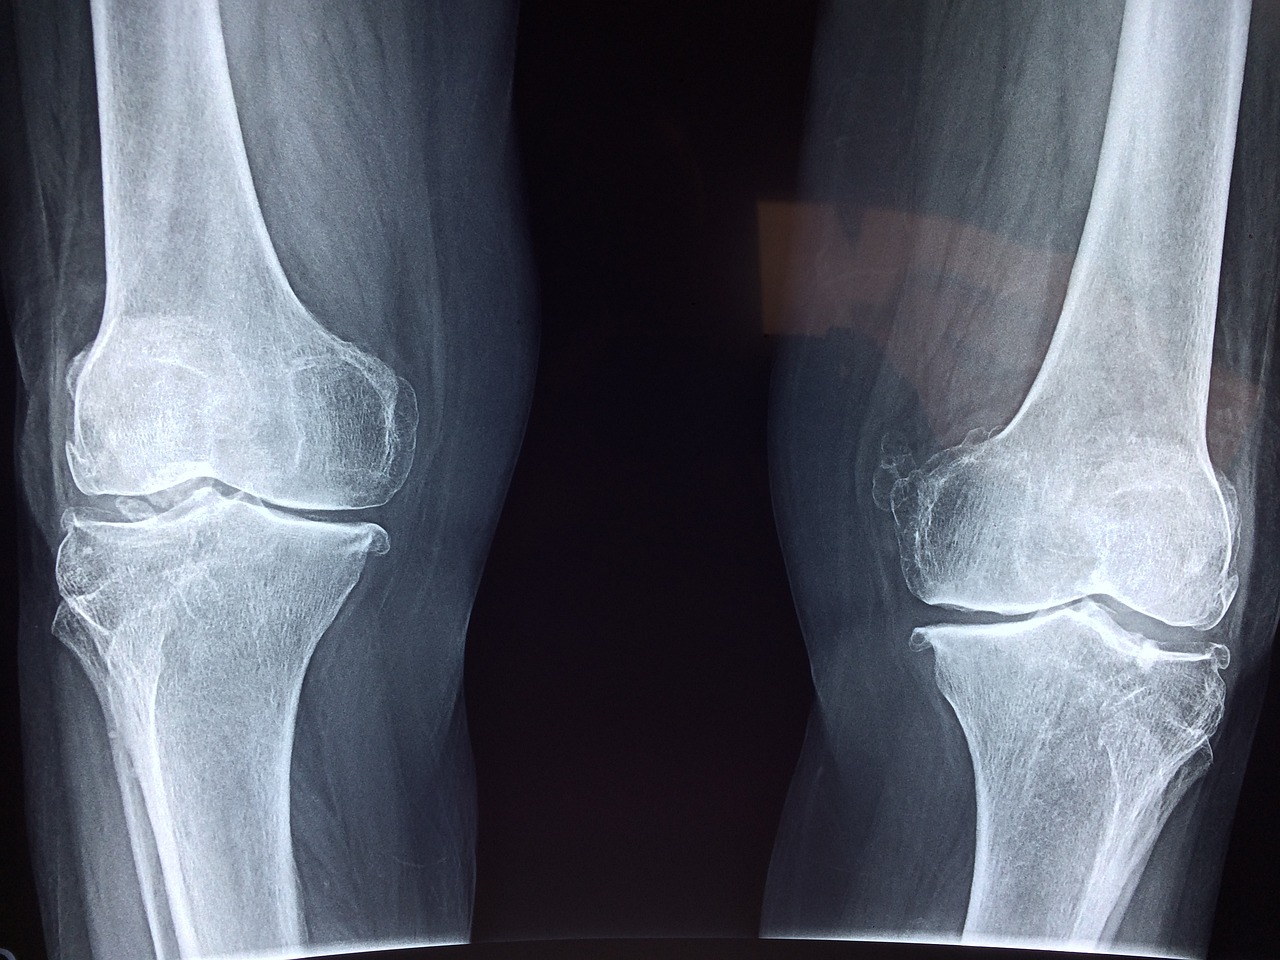

콘드로이친은 우리 몸의 연골 조직에서 발견되는 성분으로, 관절을 부드럽게 유지하고 충격을 흡수하는 데 중요한 역할을 합니다. 나이가 들면서 체내 콘드로이친의 양이 감소하게 되는데, 이는 관절이 약해지고 퇴행성 관절염과 같은 질환이 발생하는 원인이 됩니다. 따라서 이를 보충해주는 콘드로이친 영양제를 섭취하면 관절 건강을 유지하는 데 도움이 됩니다.